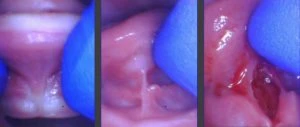

They think they are getting it all, but in reality, if you were to lift up on the tongue, it ends up looking like this:

See that thick band of tissue left behind? That’s going to limit mobility and function- and it’s not going to have nearly the success rate.

When we use our technique to get a full release, every time, we get a nice diamond-shaped wound that allows for the full lift of the tongue with minimal to no bleeding.